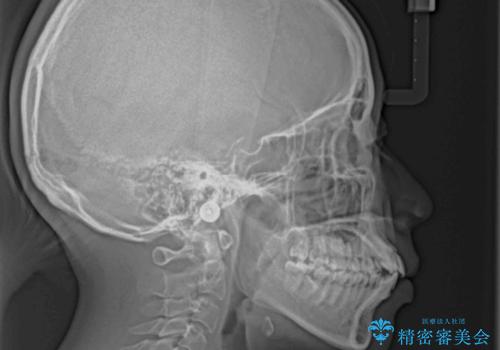

- 前歯の出っ歯と口元の閉じにくさを気にして来院された患者様です。

口元を積極的に引っ込めるために、上下左右の小臼歯4本を抜歯することとしました。

4本の歯を抜歯したことで、飛び出していた口元が引っ込み、横顔の印象が大きく改善されました。